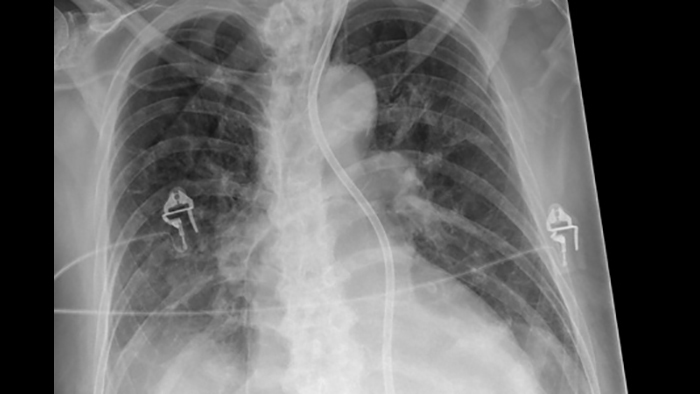

Improve your ability to provide confident diagnosis with two new image processing features

Philips UNIQUE 2 improves image quality with more homogeneous black backgrounds, reduced noise and automatic enhancement of small details

Philips Bone Suppression3 helps remove bone structures from chest images for an unobstructed view of soft tissue and can improve actionable nodule detection by up to 16.8% without the need to expose the patient to additional X-ray dose.4

Next generation image processing with Philips UNIQUE 2

Philips Bone Suppressionimproves actionable lung nodule detection up to 16.8%4